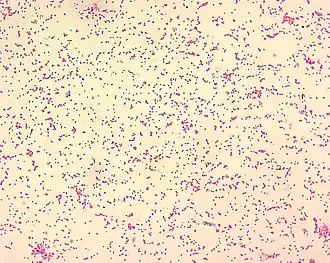

Gramnegativně zbarvené bakterie Brucella spp. pod mikroskopem (velikost bakterií na obrázku je 0,5–0,7 × 0,6–1,5 µm) | |

Brucelózu způsobují bakterie rodu Brucella. Jedná se o gramnegativní, tyčinkovité, aerobní, nesporulující bakterie, které se v hostitelském organismu vyskytují intracelulárně (uvnitř buněk).[3] V současné době je známo celkem osm druhů brucel, které se liší především primárním hostitelem. Taxonomie brucel je dosud stále nejasná a nevyřešená.[1] Na základě sekvenace genů ribozomální RNA se brucely řadí mezi alfaproteobakterie a mají blízký fylogenetický vztah k rodům Agrobacterium, Rickettsia, Rhizobium a Rhodobacter.[7] Grimont a kol. provedli analýzu DNA více než 51 kmenů brucel a ve své práci uvádějí, že jednotlivé druhy brucel jsou si natolik fylogeneticky blízké, že se jedná o jeden druh označovaný jako Brucella melitensis s řadou různých biovarů a kmenů.[8] Kvůli rozdílům v hostitelském spektru jednotlivých druhů a rozdílům v klinických projevech však nebyl tento koncept všeobecně přijat[1] a v běžné praxi se stále používá původní druhové označení.[2]